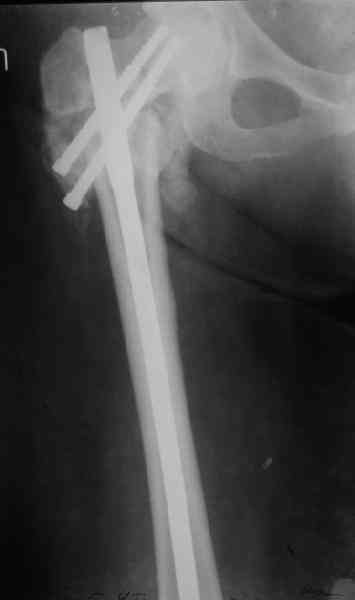

Уважаемые коллеги, хотелось бы услышать ваше мнение по следующему случаю: Относительно молодая женщина(39 лет), поступила в клинику в марте 2005 года, через 3 месяца после травмы с Неправильно срастающимся поперечным межвертельным переломом правого бедра. Был выполнен закрытый интрамедуллярный остеосинтез правого бедра канальным реконструкционным стержнем ChM. Ожидали бОльших проблем на операции, результату обрадовались. Как оказалось, зря. Сращение наступило через 3,5 месяца после операции. В ноябре 2005 года произошел перелом шейки бедра и винтов в ней. В апреле 2006 импланты были удалены. В приложении фото и рентгенограммы больной. Сопутствует ожирение 4 ст. (при росте 168 см., вес больной 140кг.), сахарный диабет II тип. Имеется медиальная неустойчивость коленного и голеностопного суставов, при нагрузке колено вальгируется на 15-20 градусов. Вопросы: 1.Целесообразность эндопротезирования (в настоящий момент передвигается на ходунках)? 2.Если ответ на первый вопрос-да, то каким протезом? 3. С какими проблемами можем столкнуться во время и после операции? Заранее благодарен за ответы. Салават Салаватов, Екатеринбург

Если осознанный выбор пациентки на лечение, то протезирование т\б сустава не таит в себе огромных сложностей - только глубина операционной раны и рубцово измененные ткани. Учитывая проксимальный дефект бедренной кости предпочтительна ревизионная ножка ZMR ZIMMER. Чашка любая безцементная.